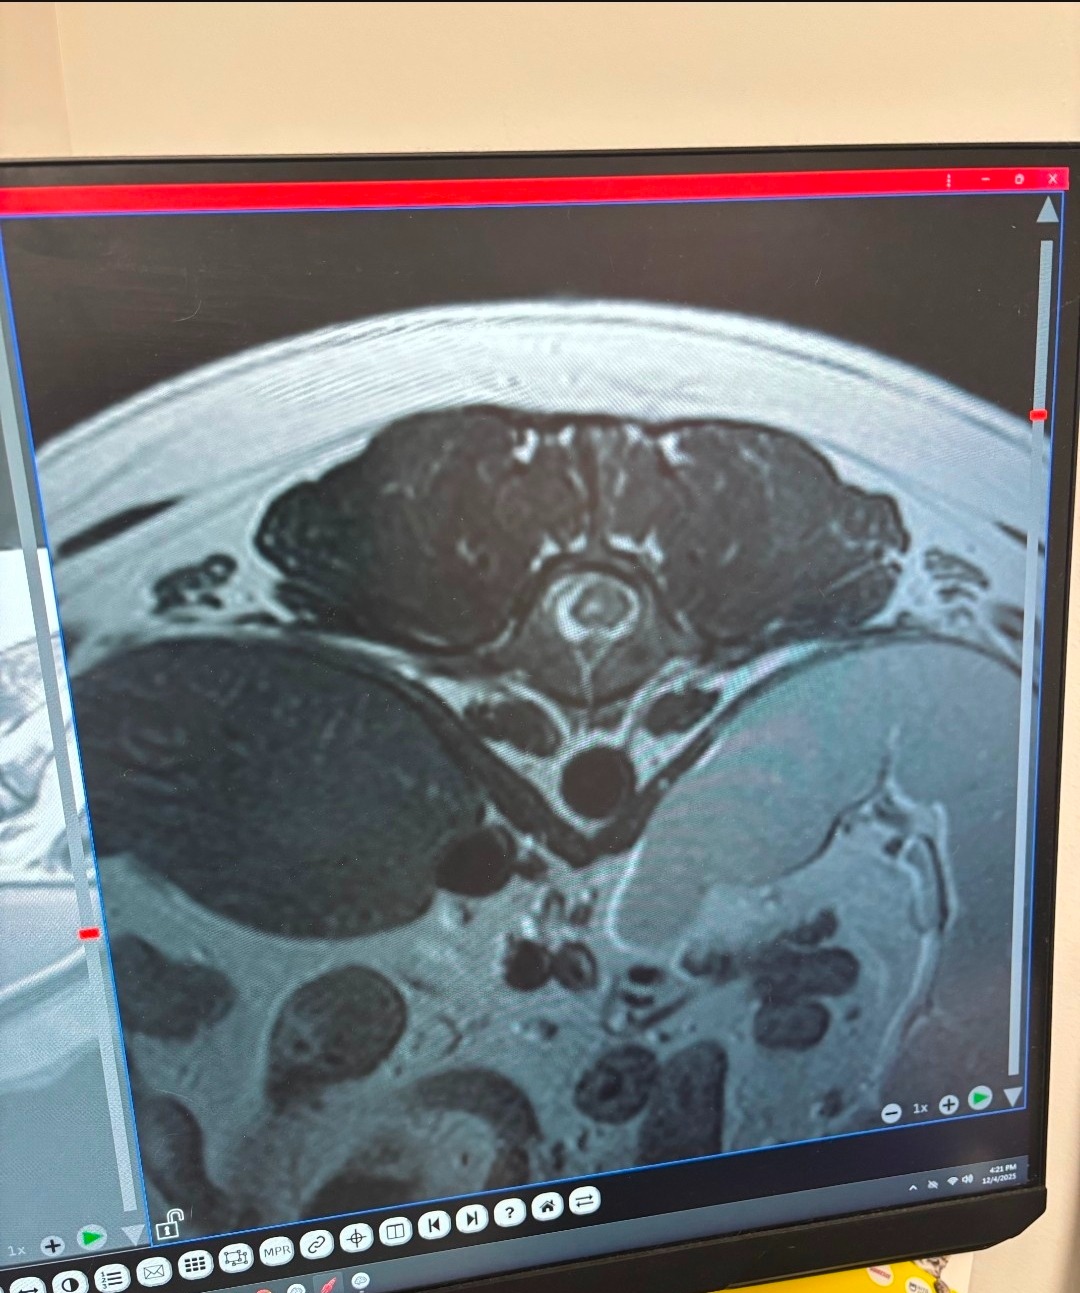

Yesterday, for reasons we still don’t understand, Lexi suddenly began yelping in pain and her legs stopped working. We stayed up with her through the night, comforting her as best we could, and brought her to the emergency vet in Richmond as soon as we could. After an MRI, the vet told us there was a 40% chance Lexi would walk again, a 40% chance she would not, and a 20% chance that she would both not be able to walk and be in pain. We made the difficult decision to attempt surgery, hoping to give Lexi the best chance at recovery. The surgery seems to have gone well, but Lexi is still not out of the woods yet and her future remains uncertain. Lexis will be five years old on January 24, 2026.